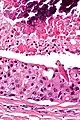

| Low magnification micrograph of a salivary duct carcinoma with characteristic comedonecrosis (left of image) adjacent to normal parotid gland (right of image). H&E stain. | |

Their histologic appearance is similar to ductal breast carcinoma.

Very low mag.